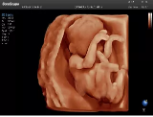

4容積探頭

積探頭是在二維圖像的基礎上,將連續(xù)采集的空間分布位置,經(jīng)過計算機重建算法,從而獲得完整的空間形態(tài)。

適用于:胎兒面部、脊柱和肢體等。

優(yōu)勢特點:快速獲取、掃查連續(xù)均勻、解剖結(jié)構(gòu)顯示為容積數(shù)據(jù)、準確進行容積測量。